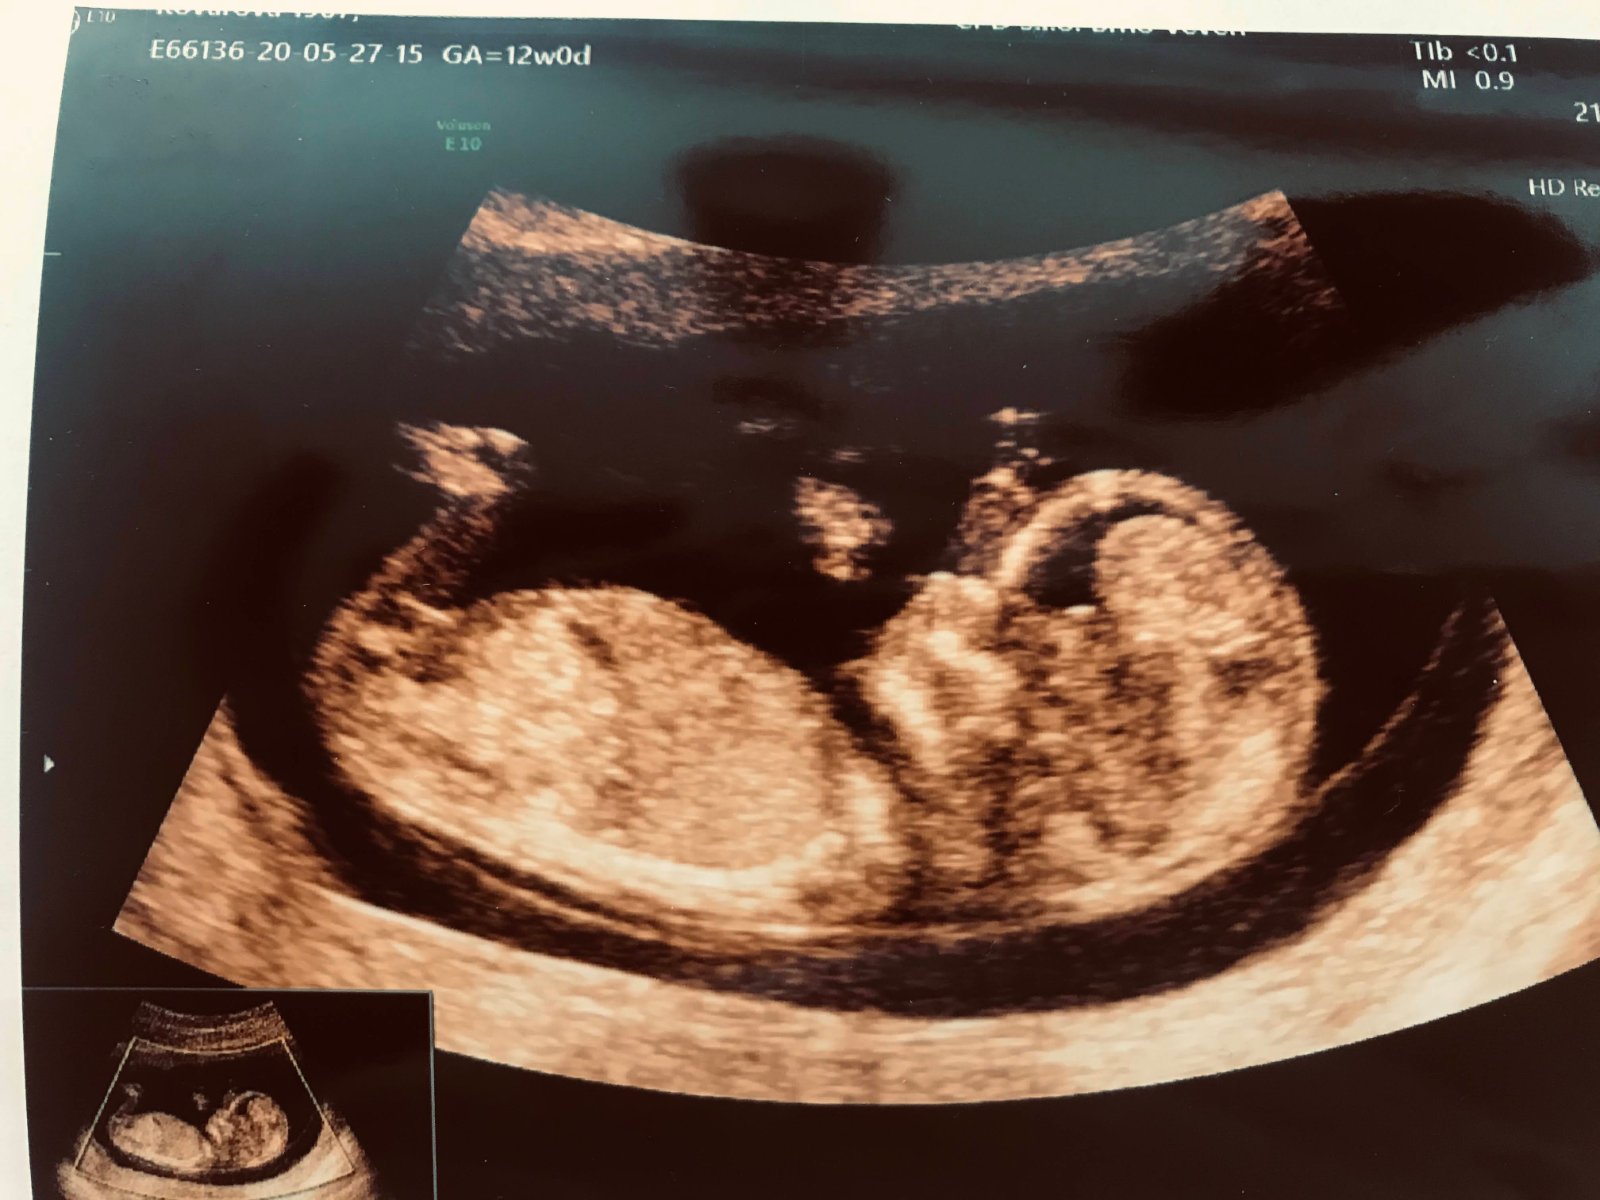

Já mám teď tady takové fotky z 12 týdne. Zítra jdu na screening tak jsem zvědavá jestli něco uvidí. Tipnete si někdo? 😃